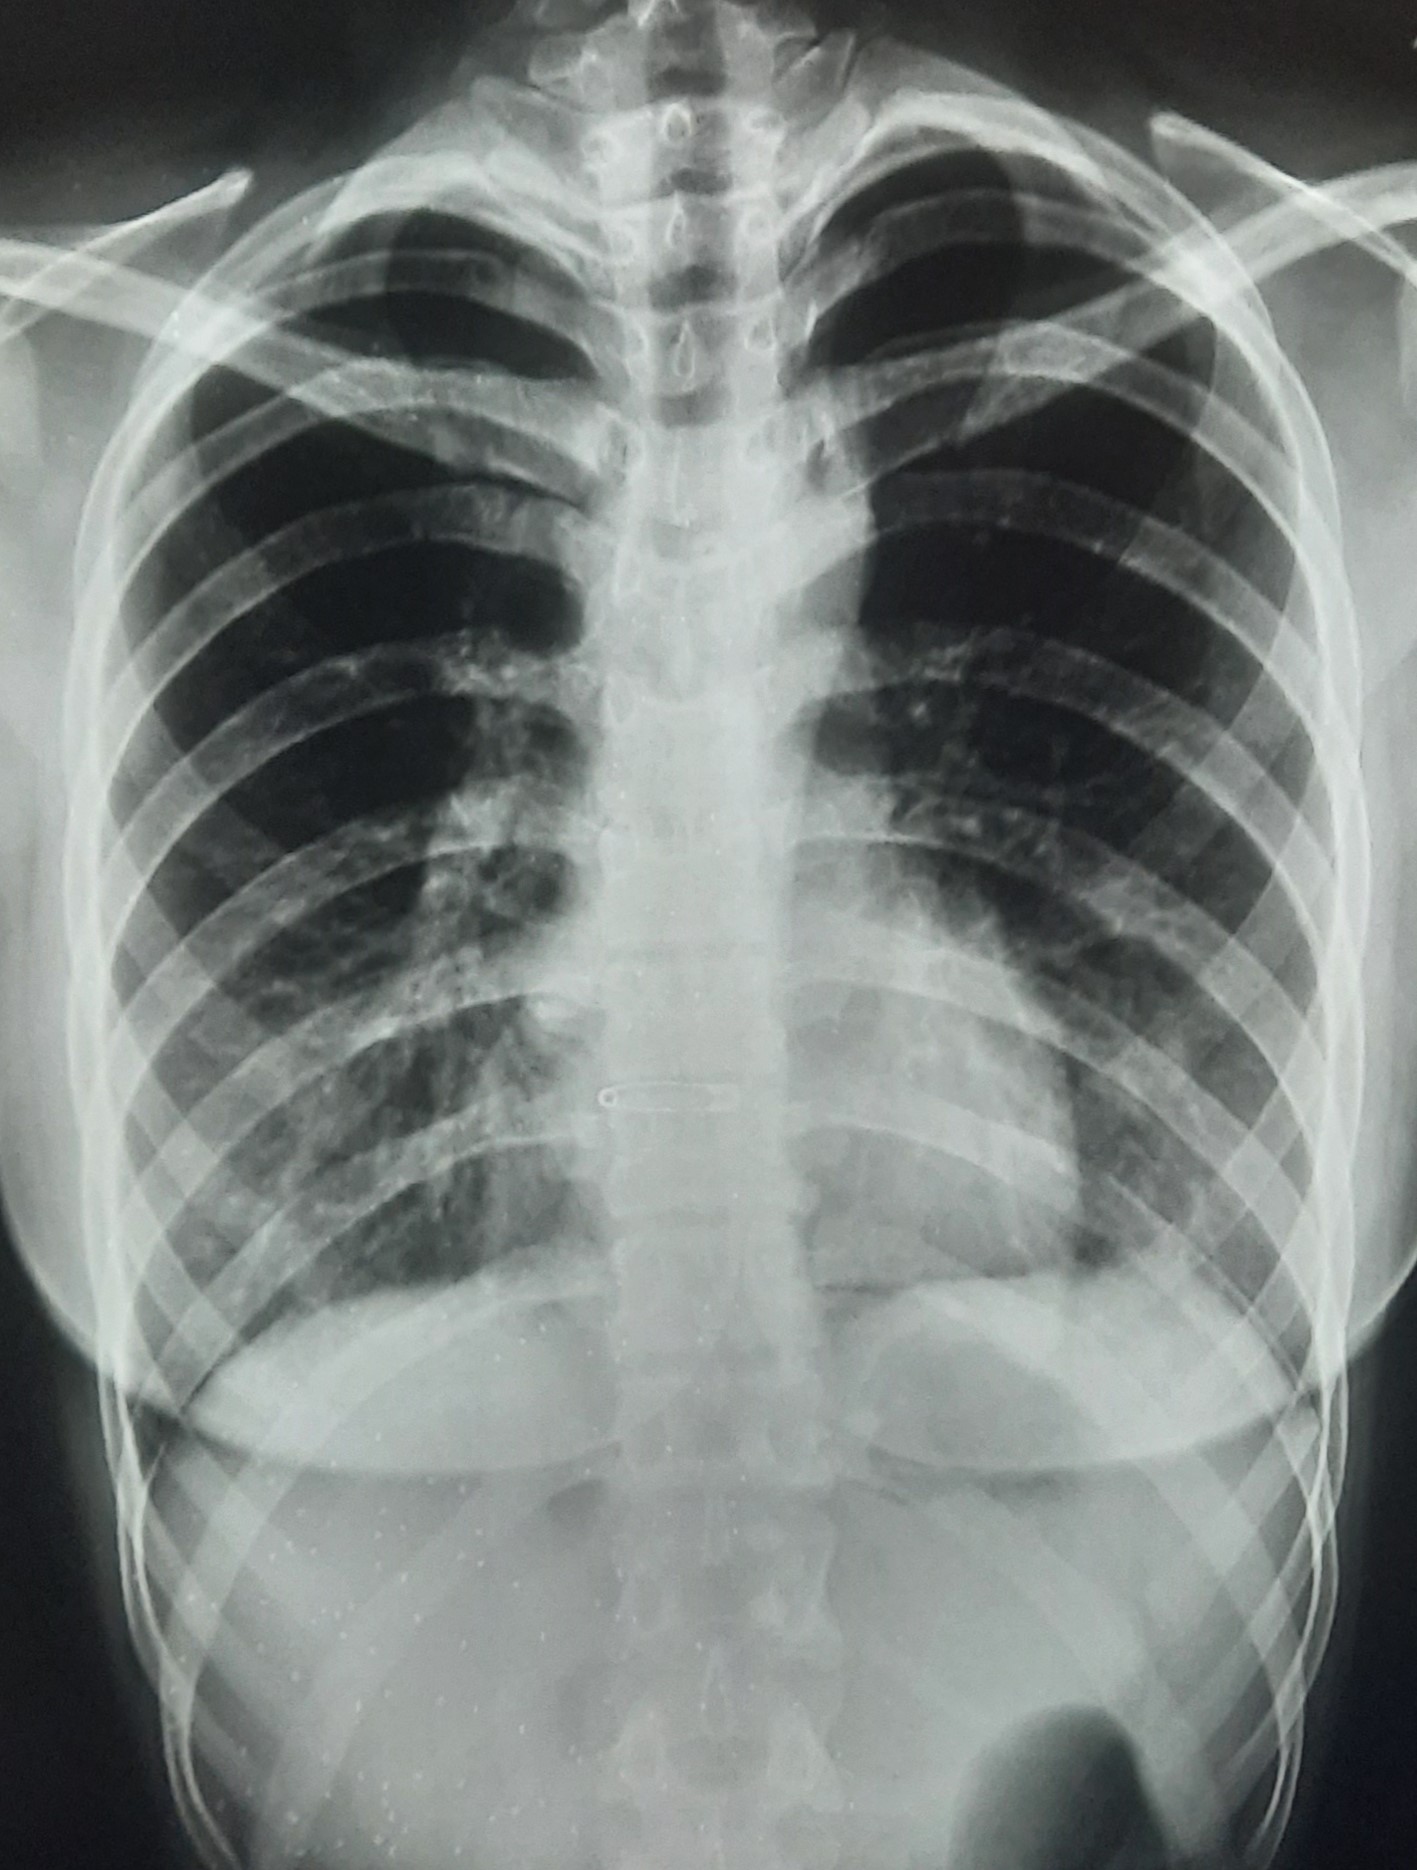

| 201 | IGGMC, Nagpur, Nagpur | P2 | 29-4271 | BUSHRA KHAN | Consent taken on Paper | 21 Yrs. |

Provisional Diag : PTB?

Final Diag : RIGHT SIDED CLINICALLY DIAGNOSED TUBERCULAR PLEURAL EFFUSION |

TB Case (Confirmed) | RIGHT SIDED PLEURAL EFFUSION | Abnormality visible on x-ray |